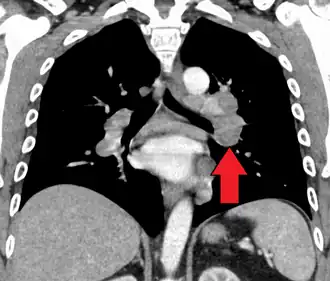

Hilar adenopathy especially on the person's left (lateral CXR) -

Hilar adenopathy especially on the person's left (coronal CT) -